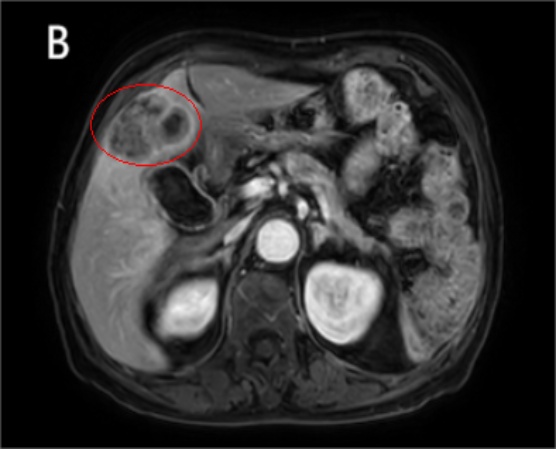

患者女性,80岁,因“右上腹隐痛20天”于2023年11月就诊于当地医院。腹部CT提示肝内占位,遂转至我院进一步诊治。患者否认恶心、呕吐、反酸、黄疸、发热、呕血、黑便等症状。既往有高血压、冠心病及脑梗死病史多年,规律服用降压药及抗血小板药物,病情稳定;无病毒性肝炎、肝硬化或长期饮酒史,家族中无肿瘤遗传倾向。入院查体:生命体征平稳,全身皮肤黏膜无黄染,浅表淋巴结未触及肿大。腹部平坦,未见静脉曲张,右上腹轻度压痛,无反跳痛及肌紧张,肝脾肋下未触及,移动性浊音阴性,肠鸣音正常。实验室检查:肝功能基本正常,直接胆红素9.00 μmol/L,白蛋白39.4 g/L,ALT、AST、ALP、GGT均在参考范围内;凝血功能正常。肿瘤标志物检测结果显示:甲胎蛋白(AFP) 2.0 ng/ml (正常值 < 7 ng/ml),癌胚抗原(CEA) 1.35 ng/ml (正常),糖类抗原CA19~98.75 U/ml (正常);乙型肝炎表面抗原(HBsAg)阴性,丙型肝炎抗体阴性。上腹部增强MRI联合MRCP显示:右肝V段见一大小约4.5 cm × 3.8 cm不规则软组织信号影,T1WI呈低信号,T2WI呈稍高信号,DWI呈明显高信号(图1)。增强扫描动脉期呈轻度不均匀强化,门静脉期及延迟期持续强化,邻近胆囊床受累,局部胆管扩张,胆囊稍增大。未见远处转移征象。初步考虑为肝内胆管细胞癌累及胆囊。经多学科团队(MDT)评估,患者心肺功能可耐受手术,无明确手术禁忌证。行剖腹探查术。术中见肝脏表面光滑,无肝硬化改变;胆囊底部与肝脏结合部有一实性肿块,直径约5 cm,质地坚硬,突出于肝表面,初步判断可能来源于胆囊或肝实质。遂行胆囊切除 + 肝S5段楔形切除术,并清扫肝十二指肠韧带周围淋巴结。术后病理检查示:肿瘤呈结节状,切面灰白、质脆(图2),镜下见大量异型明显的梭形细胞弥漫增生,核分裂象多见,伴有广泛凝固性坏死(图3)。部分区域可见残留腺样结构,提示上皮来源背景。脉管内可见癌栓形成,并见肿瘤侵犯周围神经束。肝切缘及胆总管残端未见肿瘤累及。“胆囊颈”(1/1)及“肝十二指肠韧带旁”(1/6)淋巴结见癌转移。免疫组化结果如下:细胞角蛋白(CK) (+)、CK19 (+)、CD10 (少量+);Hepatocyte (-)、Arginase-1 (-),排除典型肝细胞癌;CD31 (+)、CD34 (-)、ERG (-),排除血管源性肿瘤;Desmin (-),排除平滑肌肉瘤;Ki-67阳性指数约70%,提示极高增殖活性。结合组织形态学与免疫表型,最终诊断为:原发性肝肉瘤样癌(HSC),结节型,低分化,伴脉管癌栓、神经侵犯及区域淋巴结转移(pN1)。

注:肝4b、5段SHC,肿瘤呈结节状,切面灰白、质韧。

Figure 2. Postoperative specimen

2. 术后标本

本病例术前被初步诊断为ICC,结合影像学与病理特征分析,误诊原因可归纳为三点。一是影像学征象重叠,患者增强MRI示右肝Ⅴ段病灶呈T1WI低信号、T2WI稍高信号、DWI高信号,增强扫描动脉期轻度不均匀强化,门静脉期及延迟期持续强化,且伴胆囊床受累、局部胆管扩张表现,与ICC典型影像特征高度吻合;尽管文献指出肝肉瘤样癌HSC胆管扩张发生率显著低于ICC [7],但本病例直径约5 cm的较大病灶对胆管形成压迫浸润,继发胆道扩张,与ICC原发胆管受累表现难以区分。二是临床及实验室指标缺乏特异性,患者仅表现为右上腹隐痛,无恶心、呕吐、黄疸等特异症状,AFP、CEA、CA19-9等肿瘤标志物均处于正常范围,肝功能、凝血功能无显著异常,且无病毒性肝炎、肝硬化病史,缺乏指向HSC的特异性临床线索。三是病理特征的复杂性决定术后确诊的必要性,HSC确诊需依赖病理组织学与免疫组化检查,核心特征为同一肿瘤内上皮源性癌与间叶源性肉瘤样成分共存,免疫表型呈“上皮–间叶双表型”;本病例术后病理见大量异型梭形细胞弥漫增生,局部残留腺样结构,免疫组化CK (+)、CK19 (+)提示上皮来源,Hepatocyte (-)、Arginase-1 (-)排除典型肝细胞癌,结合Ki-67阳性指数约70%的高增殖活性确诊为HSC。而ICC以腺管状细胞排列、CK7/CK19/MUC1阳性为病理特征,与HSC存在本质差异,但此类特征仅能通过术后病理明确,术前穿刺活检受取材局限难以精准鉴别,这也是HSC术前误诊率居高不下的根本原因。